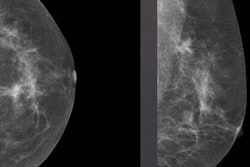

Se obtuvieron radiografías del hombro derecho del paciente. Haga clic en las imágenes siguientes para ampliarlas.